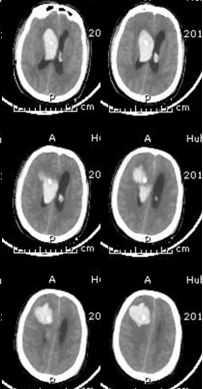

术前

术后

开颅手术具有血肿清除彻底、直视下可靠止血、去除骨瓣减压有效改善脑疝症状优点